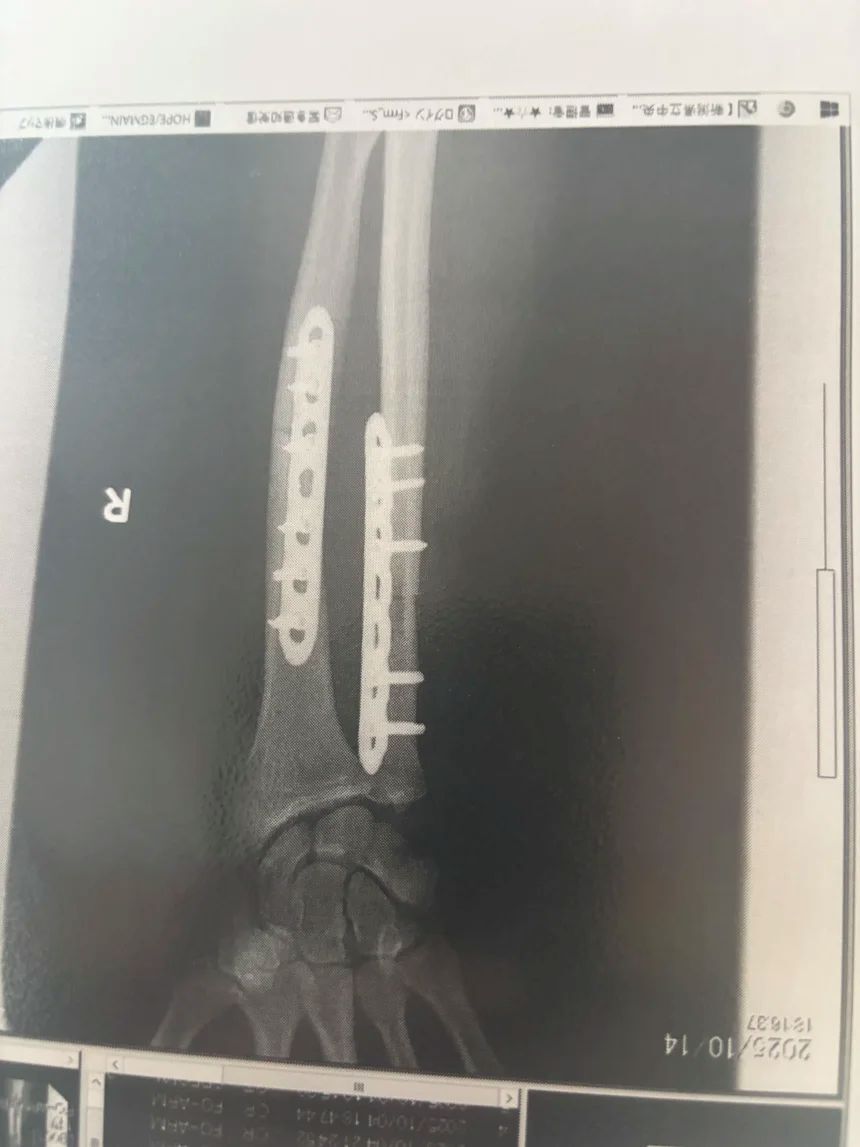

クマに噛まれた箇所に金属プレートを挿入したハロランさんの腕のレントゲン写真/Billy Halloran

この2週間、ハロランさんは病院で療養している。負傷した腕への金属プレート挿入を含む3度の手術を受けた後、CNNの取材に応じた。